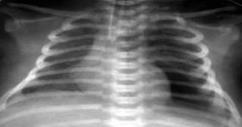

Резкое снижение пневматизации легких, воздушные бронхограммы, границы сердца не различимы, "белые лёгкие" (Рис.7).

Рисунок 7

.

РДС. Рентгенограмма грудной клетки в прямой проекции, в горизонтальном положении. Интенсивное мелкоточечное затемнение легочных полей - симптом "матового стекла", на фоне которого не дифференцируется тень средостения. Визуализируются линейные просветления, обусловленные заполненными воздухом бронхами - "воздушная бронхограмма". (

Диагностика и лечение РДС недоношенных // метод. рекомендация, 2007)